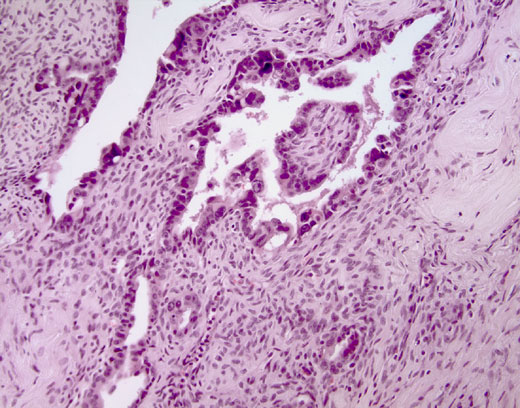

Cross-section #37 - 20X

click on the slide photo to see 40X magnification